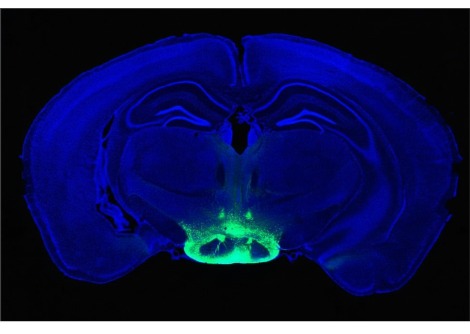

أظهر المختبر أن خمسة خيوط من microRNA تنظم إنتاج هذا الهرمون - والتي توجد في الكروموسوم 21 - معطلة. هذا الكروموسوم الزائد يؤدي بعد ذلك إلى تشوهات في الخلايا العصبية التي تفرز GnRH. تم تأكيد هذه النتائج على المستويين الجيني والخلوي. تمكن علماء Inserm من إثبات أن النواقص المعرفية والشمية التي لوحظت في الفئران كانت مرتبطة ارتباطًا وثيقًا بإفراز GnRH المختل وظيفيًا.

تمكن علماء Inserm بعد ذلك من إثبات أن استعادة وظيفة نظام GnRH الفسيولوجية تستعيد الوظائف الإدراكية والشمية في الفئران ثلاثية الذرات.

لذلك قرر الباحثون اختبار فعالية علاج GnRH النابض على العجز الإدراكي والشمي ثلاثي الزوايا في الفئران ، باتباع بروتوكول مماثل لتلك المستخدمة في البشر. بعد 15 يومًا ، تمكن الفريق من إثبات استعادة الوظائف الشمية والمعرفية في الفئران.